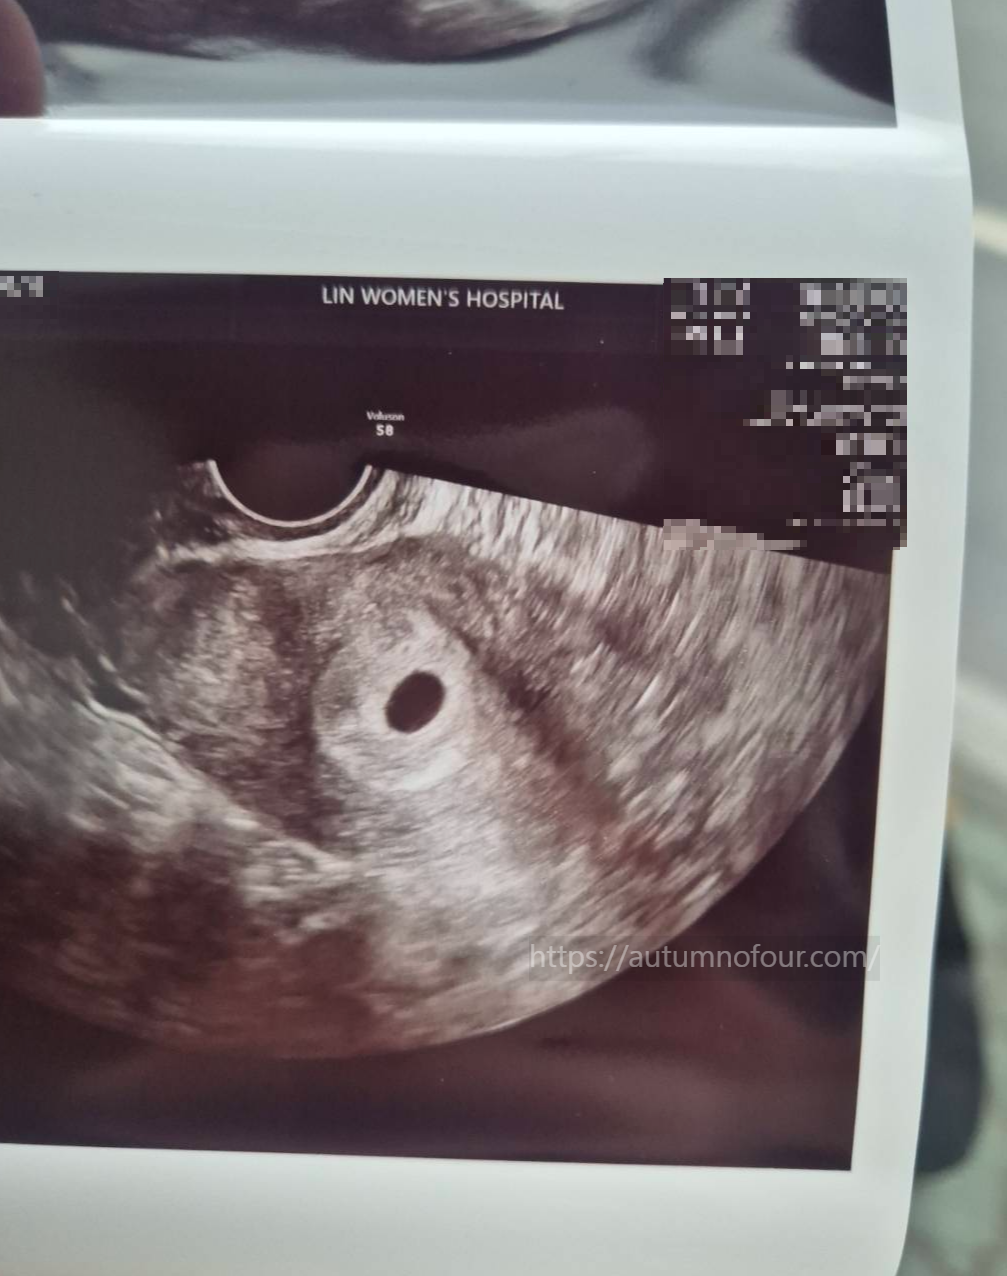

5. 옷을 갈아입고 나오니, 초음파 사진이 뙇!

아기집이 똥~그랗게 뙇!!

10mm의 아주 귀엽고 작은 아기집이 자궁에 아주 잘 자리잡고 있었다.

드뎌 아기집을 보다니.

6. 이제 다음주엔 난황과 아기(?)를

그 다음주엔 심장소리를 들을 수 있다고 하셨다.